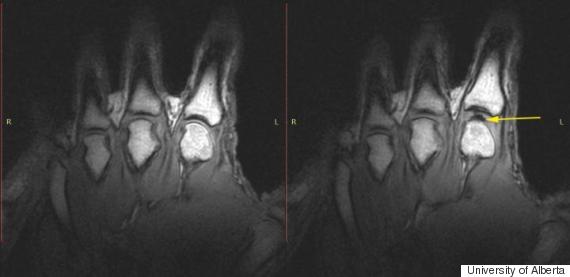

Əvvəla barmaqlarımızı

şaqqıldatdığımızda nələr olduğuna baxaq. Maye ilə dolu olan iki sümüyün birləşdiyi

oynaq kapsulundakı boş qisim, barmaqlarımızı hər şaqqıldatdığımızda genişlənir

və burdakı maye, sümüklərin arasındakı boşluğu doldurmaq üçün kifayət etmir. Təzyiqin

düşməsi və sonrasında yaranan qaz dolu qabarcıq, barmaqları şaqqıldatdığımız

vaxtdakı o məşhur səsin çıxmasına səbəb olur. Yəni bu səsin arxasındakı tək şey

bir qabarcıq dənəsidir.